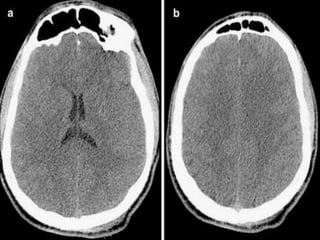

Which one is CT brain

How to differentiate CT from MRI

• Bone is dense(white) on CT brain while hypo

intense(dark) on MRI(outer bright signals on

MRI are due to subcutaneous fats).

• Grey-white matter differentiation is clear on

MRI compared to the CT.

• Presence of periventricular lucent areas in

MRI.

• MRI usually have multiple films compared to

commonly single in CT